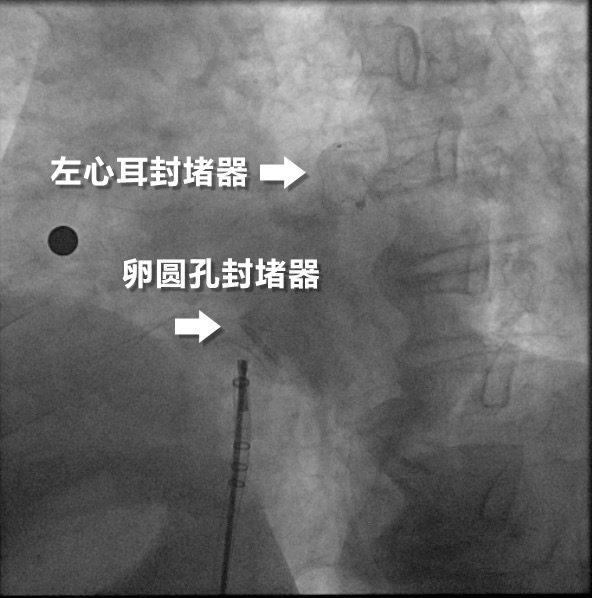

X线下的双封堵器

手术中,何奔教授团队在腔内超声影像引导下,巧妙通过卵圆孔送入输送鞘,率先植入左心耳封堵器,精准封闭房颤血栓的主要来源。随后,又植入卵圆孔未闭封堵器,成功闭合心脏房间隔的异常通道。术后即刻显示,两枚封堵器位置理想,无残余分流。